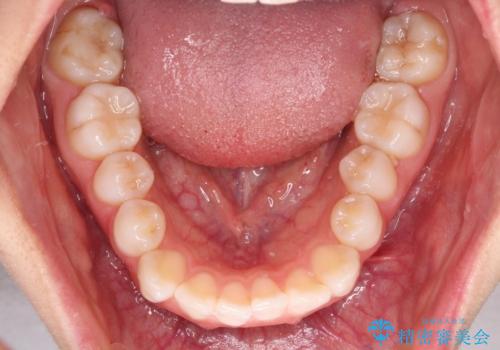

- クリアブラケット

- 1年6ヶ月

- 前歯の出っ歯と口元の閉じにくさを気にして来院された患者様です。

口元を積極的に引っ込めるために、上下左右の小臼歯4本を抜歯することとしました。

4本の歯を抜歯したことで、飛び出していた口元が引っ込み、横顔が大きく改善されました。